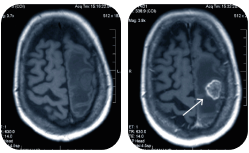

• КТ головы

КТ головы

Компьютерная томография головы в Клинике Эксперт во Владивостоке  -  это метод медицинского обследования. Его назначают, когда необходимо определить состояние костей и сосудов головного мозга.